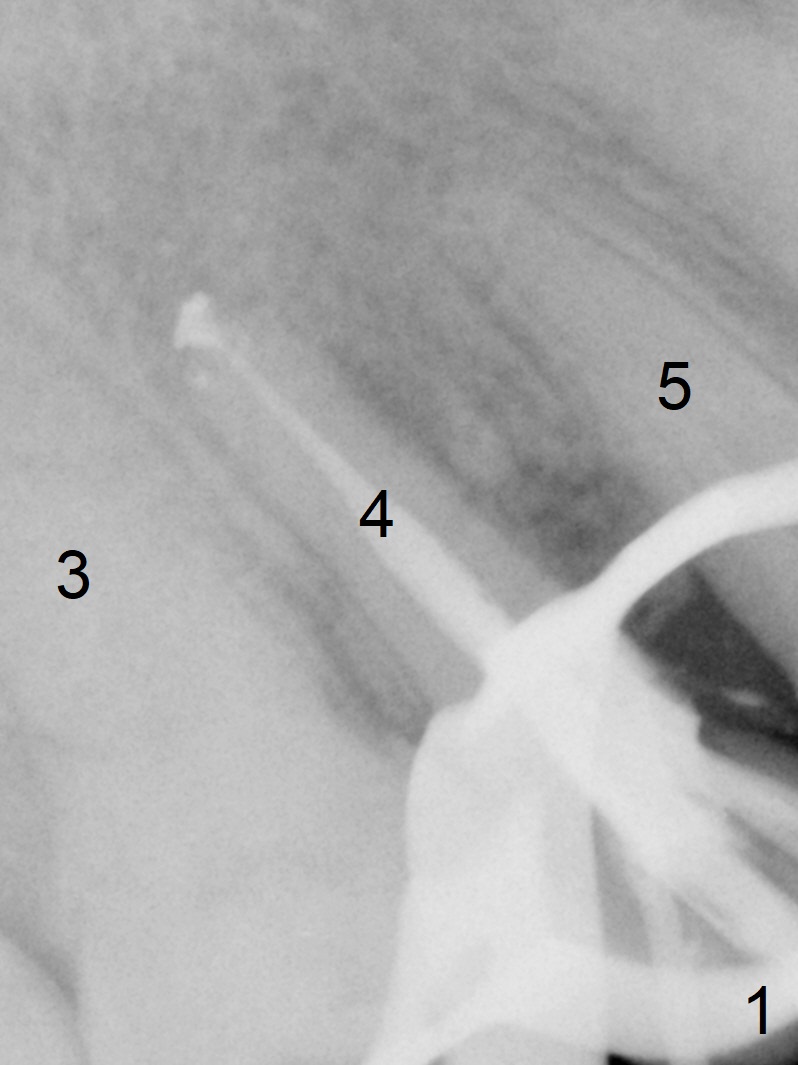

Seven years post RCT (Fig.1), the tooth #4 of a 65-year-old woman fractures subgingival palatally (Fig.2). Since the root of the affected tooth is close to the tooth #3, osteotomy is established in the mesial slope of the socket (Fig.3). Change the trajectory once the drill has penetrated the lamina dura of the socket (Fig.4). The initial depth will be 20 mm for a 3.8x16 mm implant (Fig.5).